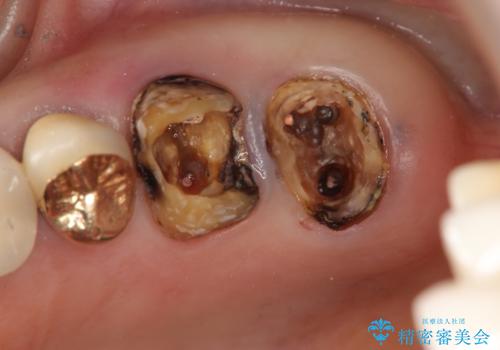

X線写真・視診より歯の破折クラウン下の虫歯再発が認められます。

クラウンの除去・虫歯の除去、根管治療を行ったのち、上顎は強い咬合力に対し破折抵抗性のある咬合面をメタルにしたメタルボンドによる補綴を計画します。